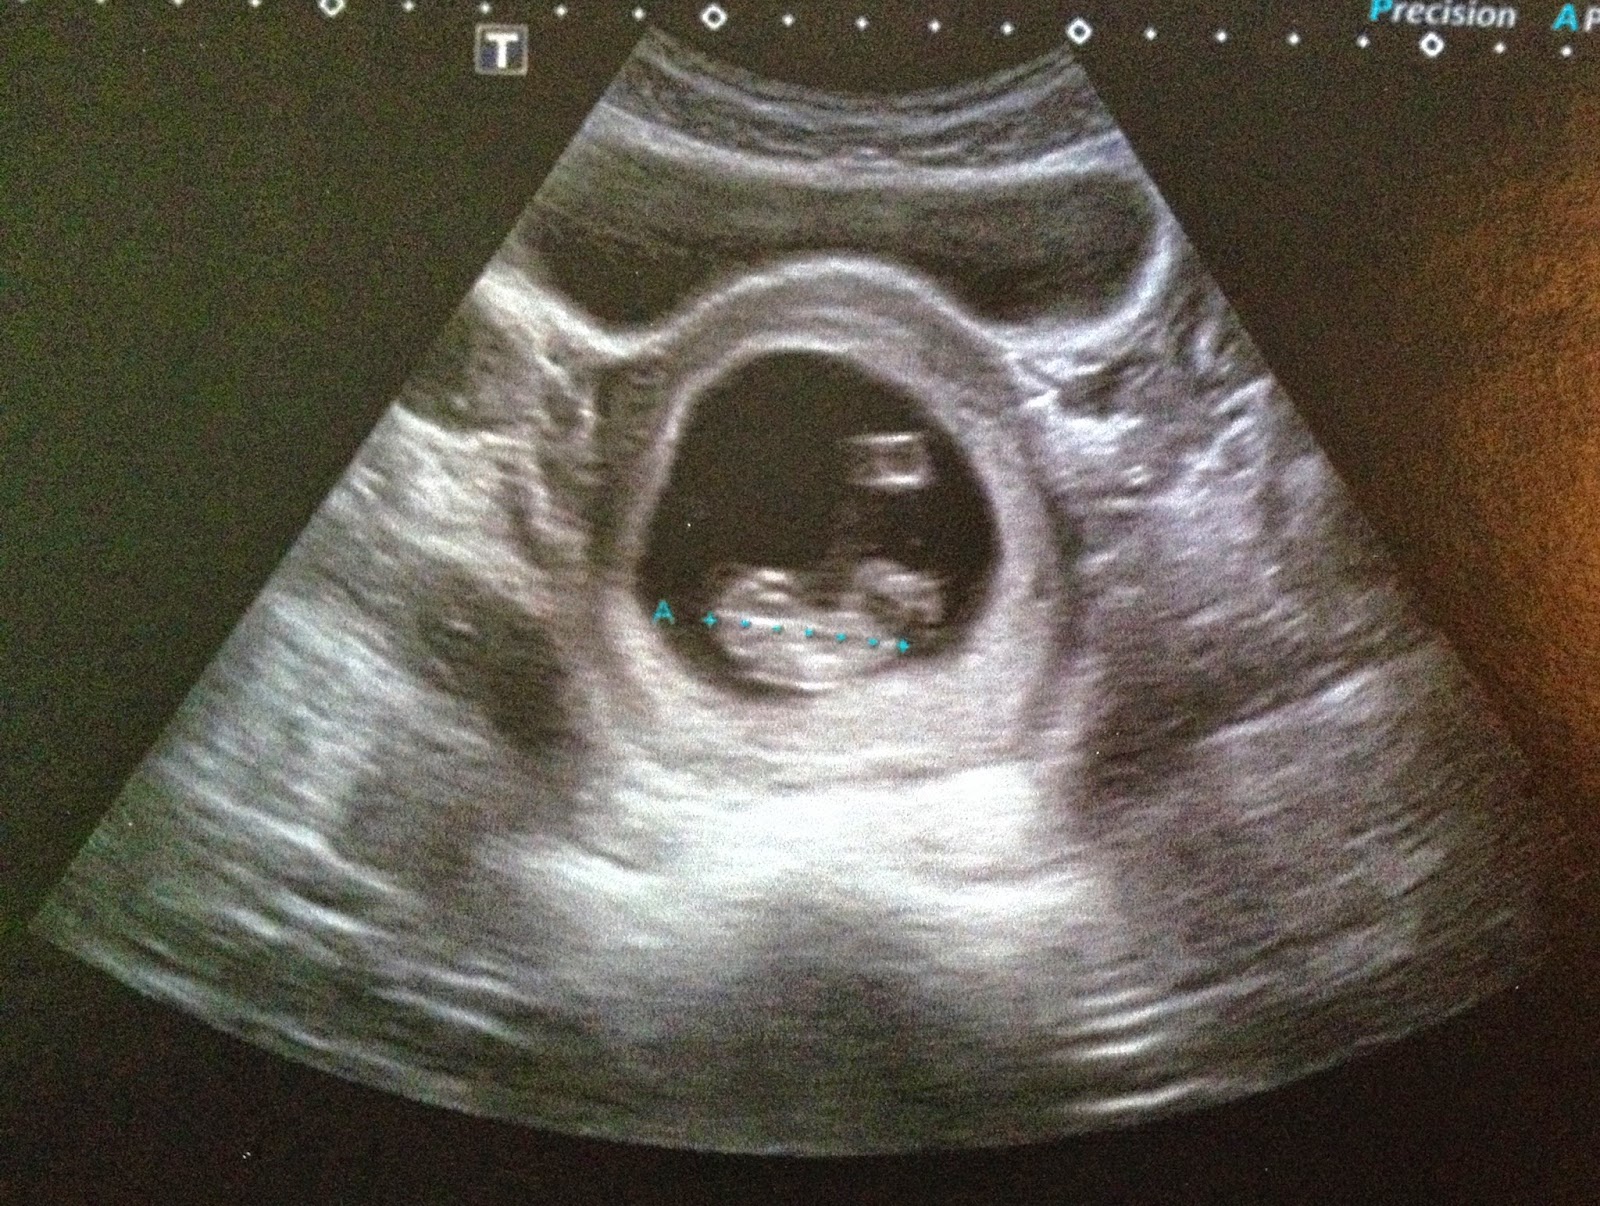

Et là on découvre un haricot, dans mon ventre, au bon endroit et on entend son coeur.

Je pense que c’est le plus émouvant, ce petit bruit qui te dit que tu es deux et que tout va bien.

Ce petit coeur qui bat vite. Le médecin peut alors dater la grossesse.

Echographie à 6 SA +/-3 jours, le 2 décembre.

Echographie à 9 SA+/- 5 jours, le 17 décembre.

Deux semaines plus tard, le bébé est daté avec 4 jours de moins et il a encore bien poussé, il a des fesses et une tête. C’était assez émouvant d’ailleurs .